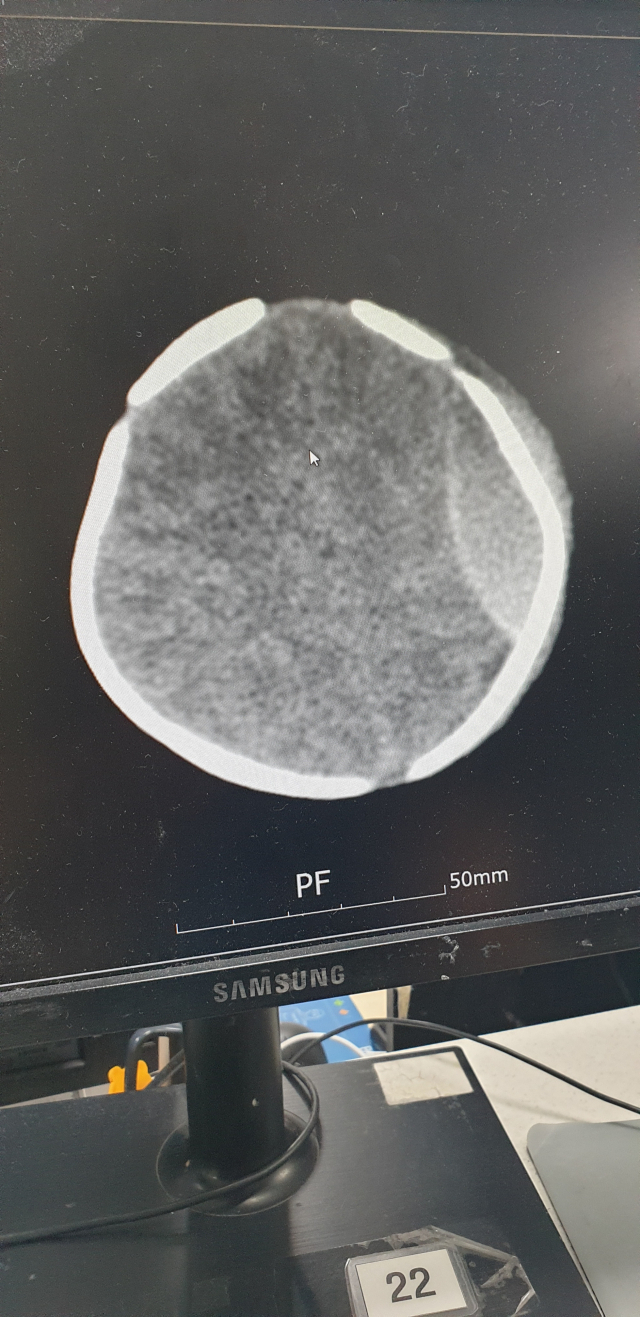

생후 13일 아기를 처치대에서 떨어뜨려 다치게 한 혐의로 산후조리원 관계자들이 금고형을 선고 받았다. 사진은 낙상 피해 아기 머리 CT 사진. 낙상 피해 부모 측 제공 생후 13일 아기를 처치대에서 떨어뜨려 다치게 한 혐의로 산후조리원 관계자들이 금고형을 선고 받았다. 사진은 낙상 피해 아기 머리 CT 사진. 낙상 피해 부모 측 제공

생후 13일 된 아기를 처치대에서 떨어뜨려 다치게 한 혐의를 받는 산후조리원 관계자들이 1심에서 금고형을 선고 받았다.

이들은 지난해 11월 28일 사하구의 한 산후조리원에서 생후 13일 된 아기를 높이 85cm의 처치대에서 떨어뜨린 혐의를 받는다. 사건 당시 이 아기를 돌보던 간호조무사는 자리를 비웠고, 그 사이 처치대 위에 혼자 있던 아기가 아래로 떨어졌다.

조리원은 사고 하루 뒤인 29일 엑스레이 검사 결과 골절상 등을 확인해 그제서야 부모에게 사고 사실을 알렸다. 아기는 뒤늦게 대학병원으로 옮겨져 수술을 받았고, 건강을 회복해 퇴원했다. 하지만 아기가 너무 어린 탓에 5살 때까지 추적 검사를 통해 지적 능력 등을 지켜봐야 한다.